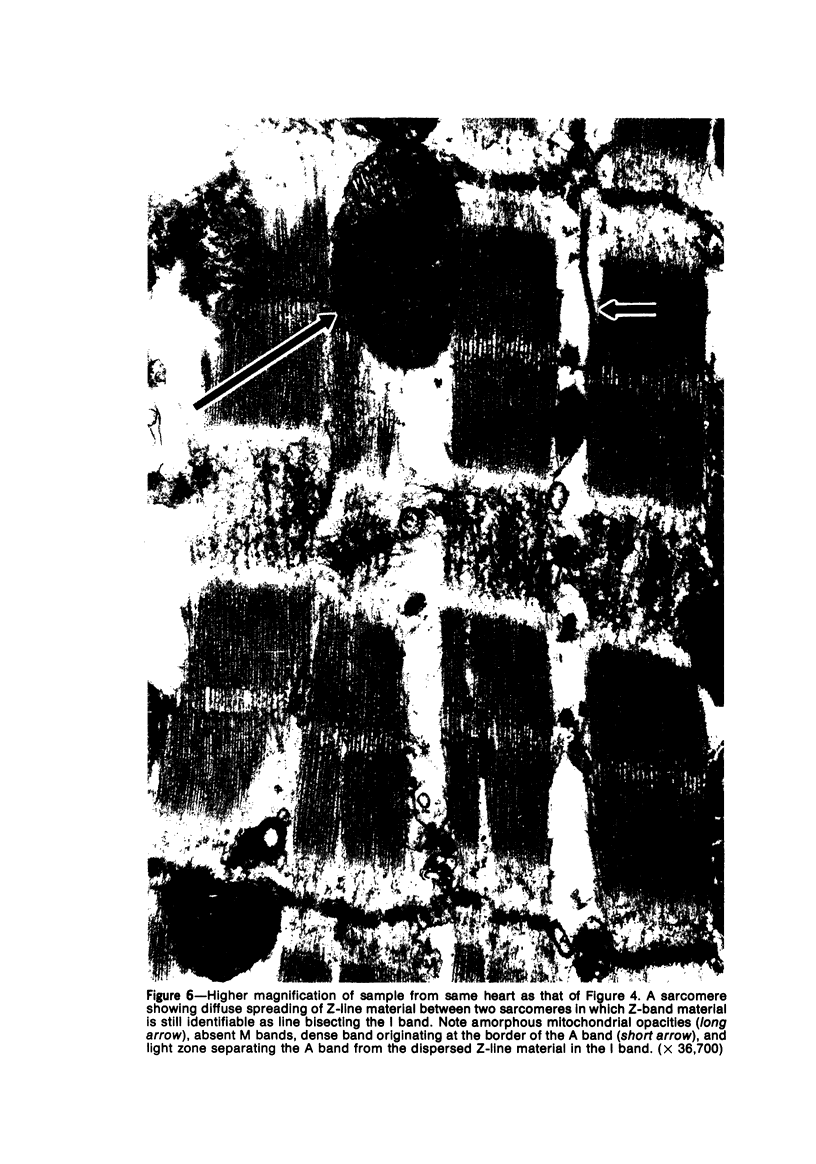

Ultrastructural changes in myocardial cells from the ischemic border of infarcts (produced in rat left ventricles by ligating the anterior coronary artery in vivo) were examined 1 to 24 hours after ligation. Twenty-four hours after ligation, irreversibly injured cells showed a selective spreading of Z-band material over the I band; disappearance of M bands, prominent N bands, and disassembly of A bands were also noteworthy. Sixty minutes after ligation the cells of the ischemic border were ultrastructurally normal except for paradoxically relaxed sarcomeres, indicative of an inability to contract in response to the calcium influx produced by osmium tetroxide; progressive vacuolization of this zone was evident after 4 to 12 hours. Paradoxical relaxation may be an ultrastructural correlate of acute ischemic "pump failure".